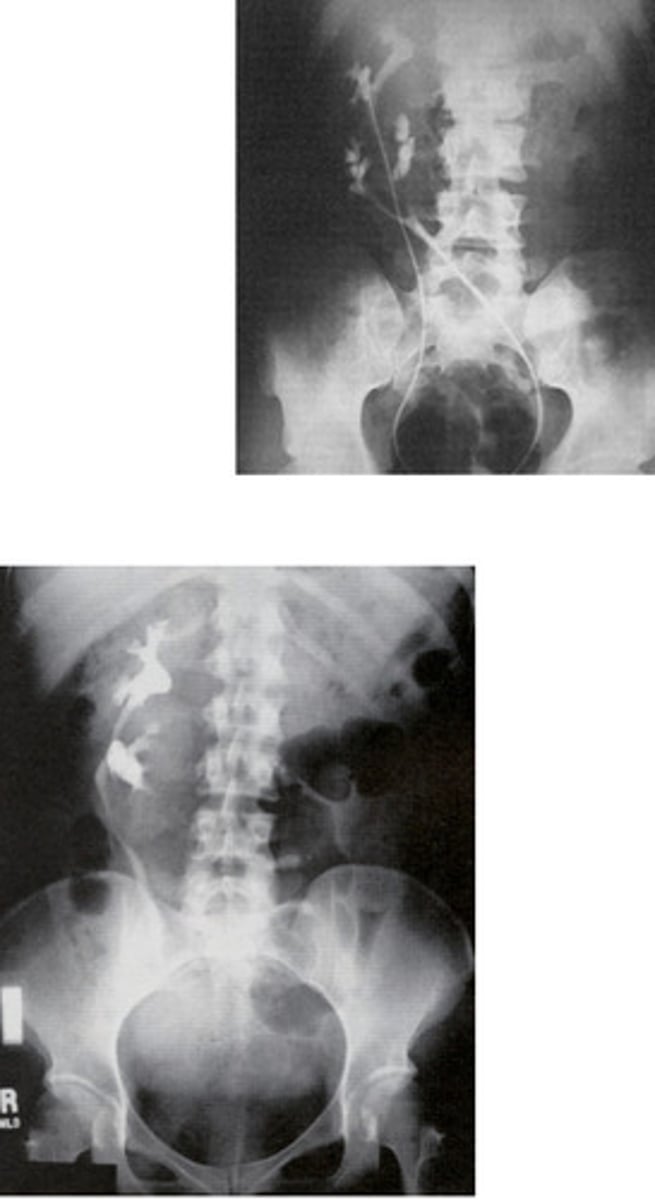

- Pelvic Kidney

- Pelvis

- What congenital anomaly refers to a type of ectopic kidney that is located in the pelvis and has a short ureter?

- When patients need a renal transplant, where are they placed?

- Horseshoe Kidney

- Kidney stones

- What congenital anomaly occurs when the lower poles of the kidney fail to separate in the fetus and results in a horseshoe-shaped kidney?

- What can patients frequently develop because the ureters are displaced with this pathology?